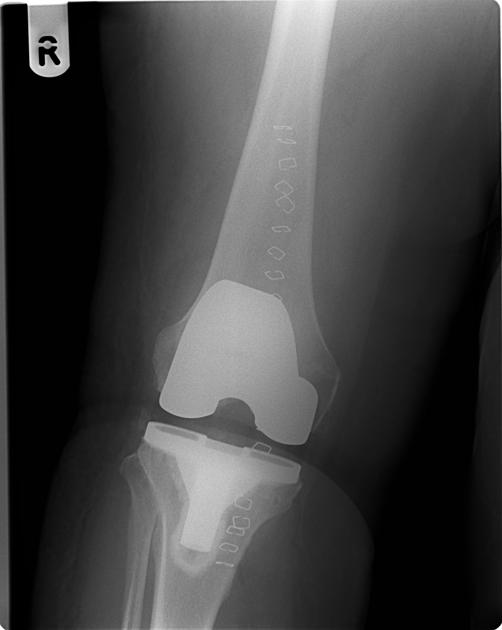

Diagnosis

Total knee replacement